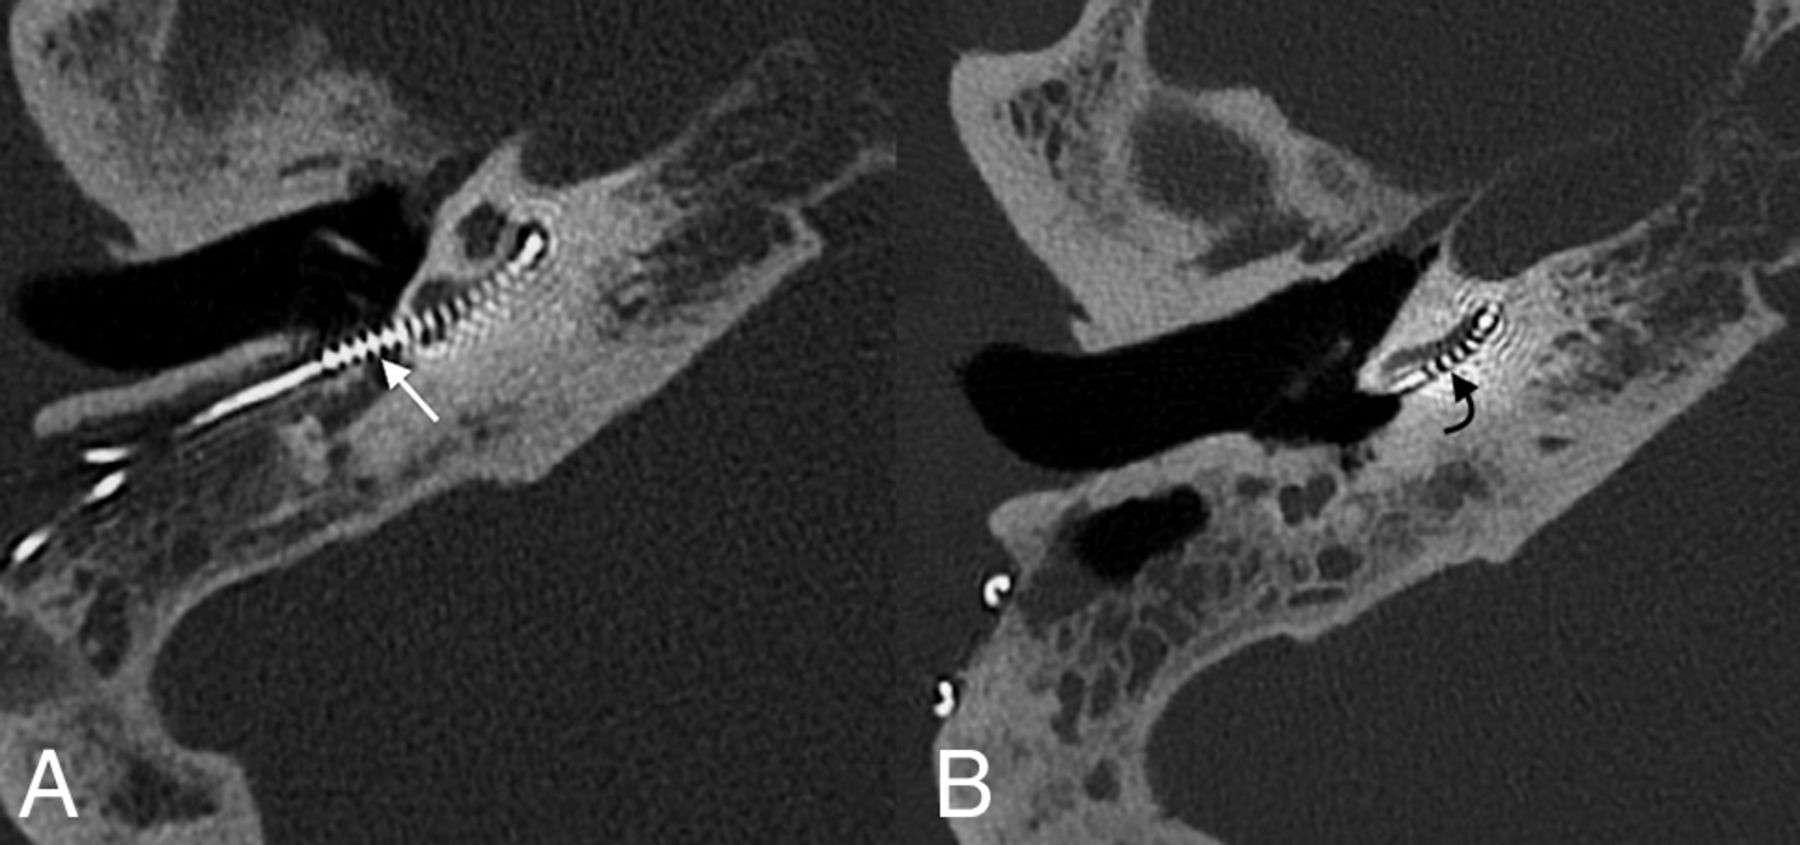

Regardless of the cochlear entry point, complications do occur. The electrode can kink, flip over at its tip, or migrate.68,69 Postoperative imaging can also demonstrate various degrees of electrode displacement, including within the semicircular canal, internal carotid artery, internal auditory canal, and vestibule.69,70 Across time, electrodes may also migrate from their initial position (Fig 13). Postoperative images should be evaluated in the context of the surgical approach (ie, via the round window or adjacent cochleostomy) and should include an assessment of electrode position, integrity, and change since prior examinations.

A 64-year-old woman who had poor progress of hearing following the placement of a cochlear implant. Axial CT image at the time of presentation (A) shows that the electrode array is retracted from its expected location, with multiple electrode leads located outside of the cochlea (straight white arrow). Follow-up imaging after surgical revision (B) shows normal positioning of the implant, with the first electrode located approximately 4 mm past the round window (curved black arrow).